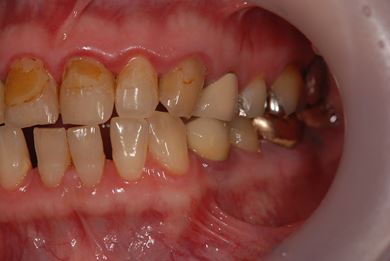

| 性別/年齢 | 女性 / 51歳 | ||||||||||||||||||||||||||||||||

| 主訴 | 前の歯の治療後の変色が気になる。詰め物がとれた箇所あり。痛みあり。 | ||||||||||||||||||||||||||||||||

| 治療方針 | セラミック治療にて、審美的回復を行う。 | ||||||||||||||||||||||||||||||||

| 治療内容 | オールセラミッククラウン7本(オールセラミック用土台1本)、ハイブリッドセラミッククラウン10本(ハイブリッドセラミック用土台9本)、ハイブリッドセラミックインレー1本 | ||||||||||||||||||||||||||||||||